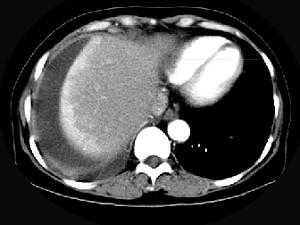

问题 女,59岁,发热、右上腹痛、右下肺呼吸音低,影像检查如图,最可能诊断是 ( )

选项 A、肝硬化腹水 B、大网膜膈下间位 C、膈下脓肿 D、肝包膜下出血 E、腹腔积液

答案 C